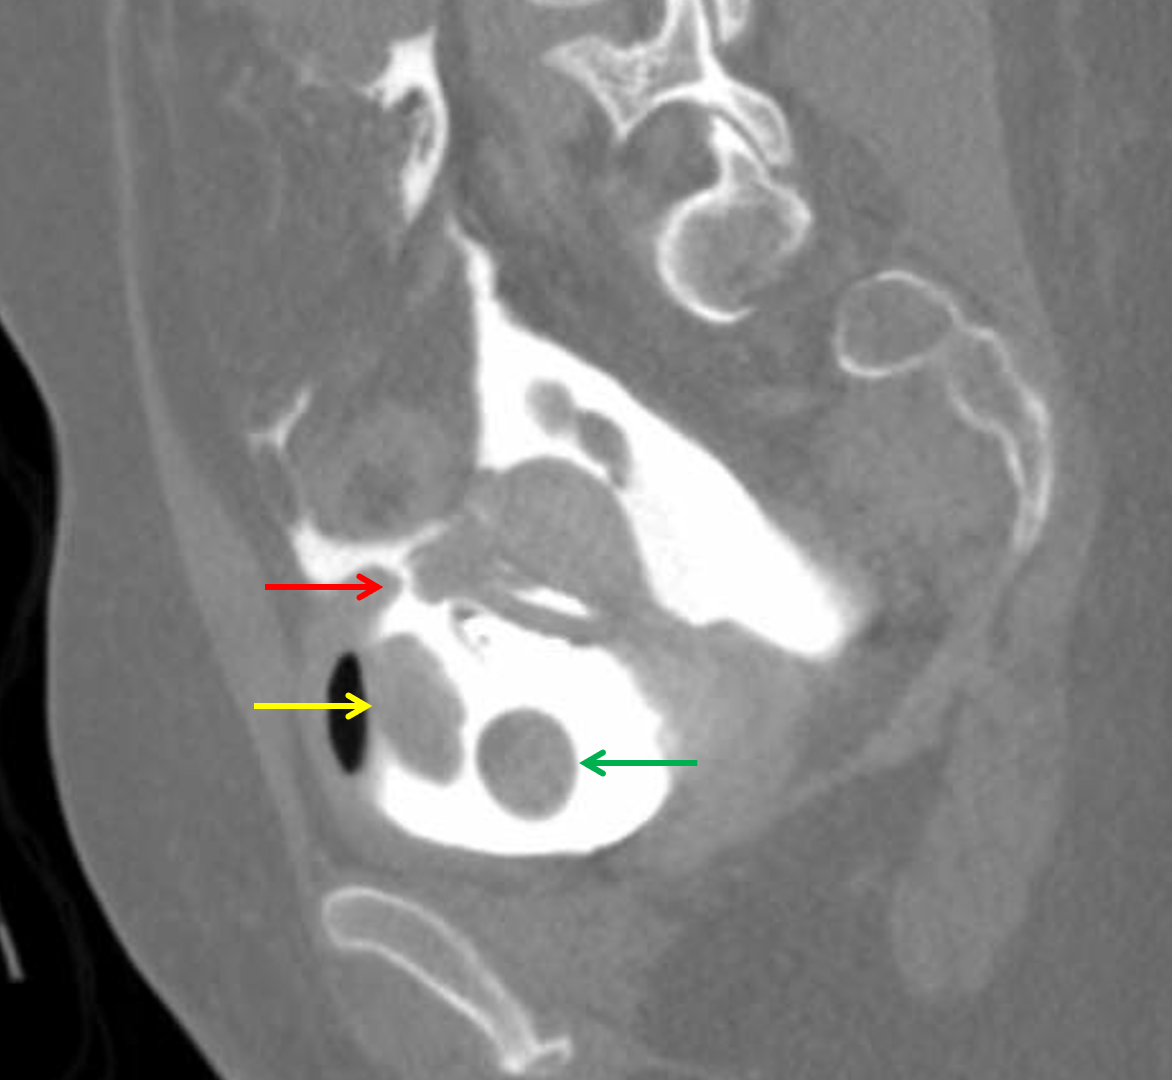

from pocusjournal.com

Delayed Iatrogenic Bladder Rupture Diagnosed by POCUS in the Emergency